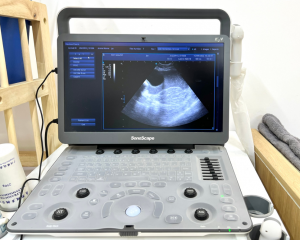

Máy siêu âm Sonoscape E2V

- Thực hiện các thao tác về chẩn đoán hình ảnh như siêu âm, chụp x-quang.